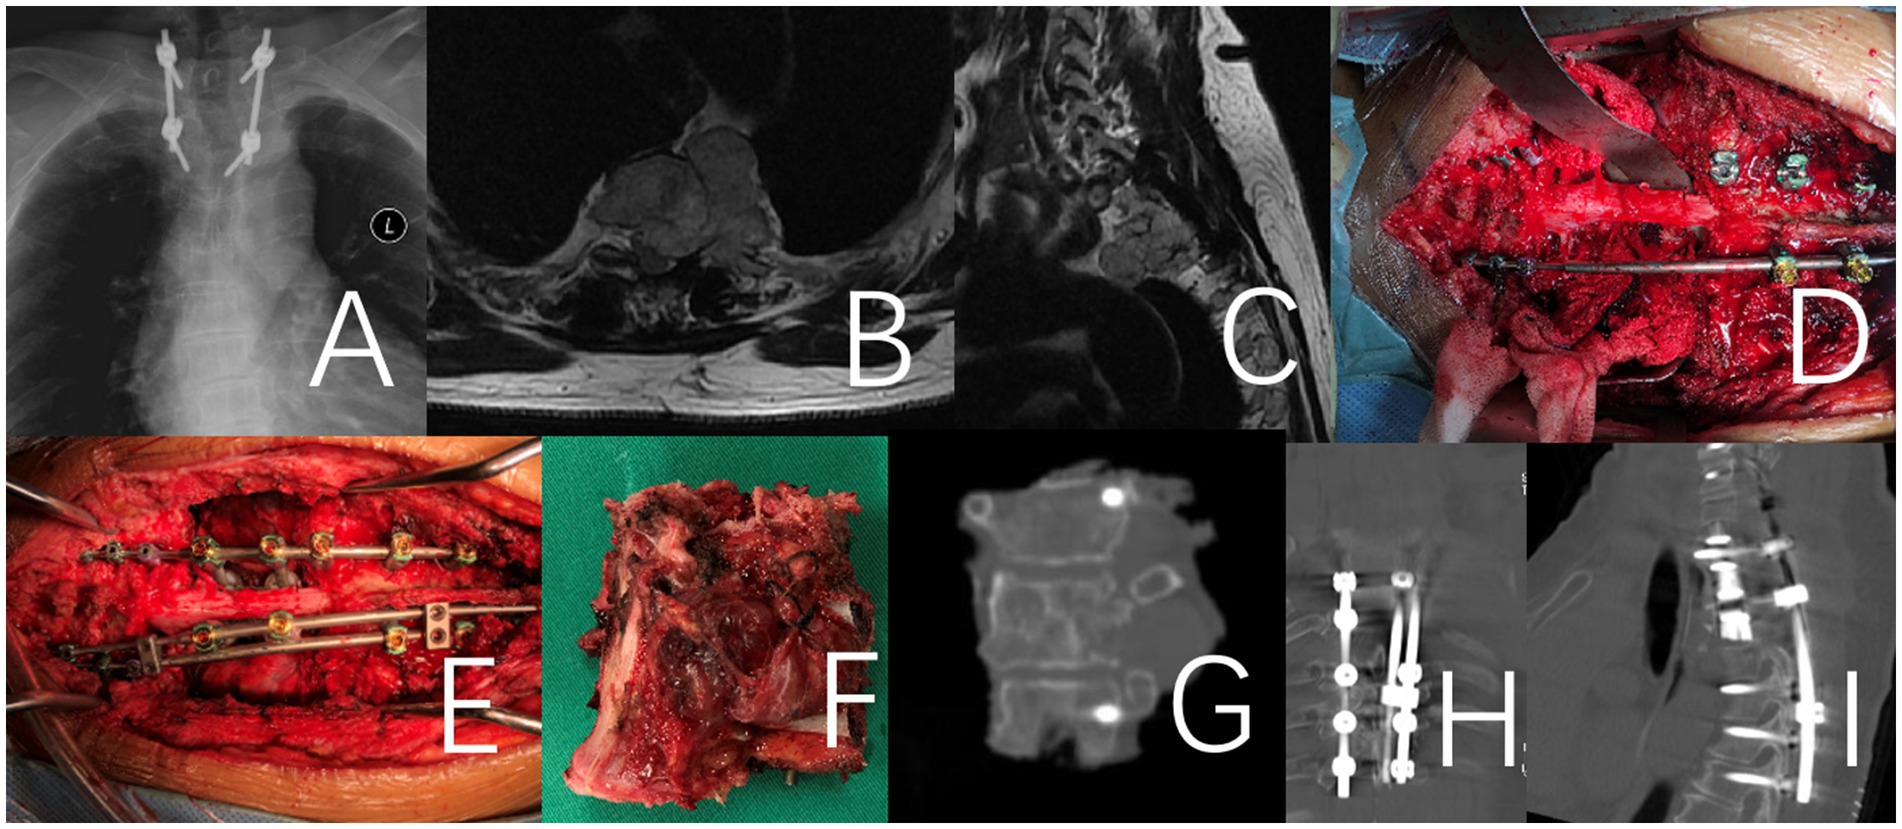

Figure 2. This case involves a 71-year-old female patient with a large T2 chordoma, classified as WBB stage T2 5–12 (A–E). The patient underwent a one-stage en bloc resection. It is a revision surgery. Initially, a T1-3 tumor resection was performed via an anterior approach. Following anesthesia preparation, the patient was placed in a supine position, and a midline anterior cervical incision was made to fully expose the affected vertebrae and adjacent segments. In the second stage of the procedure, the patient was positioned prone for a posterior approach. The T1-3 vertebrae and the tumor were removed en bloc, and a 3D-printed artificial vertebra was implanted and fixed between C7 and T4. Throughout the procedure, there was no direct intralesional operation of the tumor. (A–C) Preoperative X-Ray and MRI. (D–F) Intraoperative imaging of the specimen after removal and an anterior view of the specimen. (G) X-ray image of the surgical excision specimen. (H,I) Illustrate the internal fixation after revision surgery.